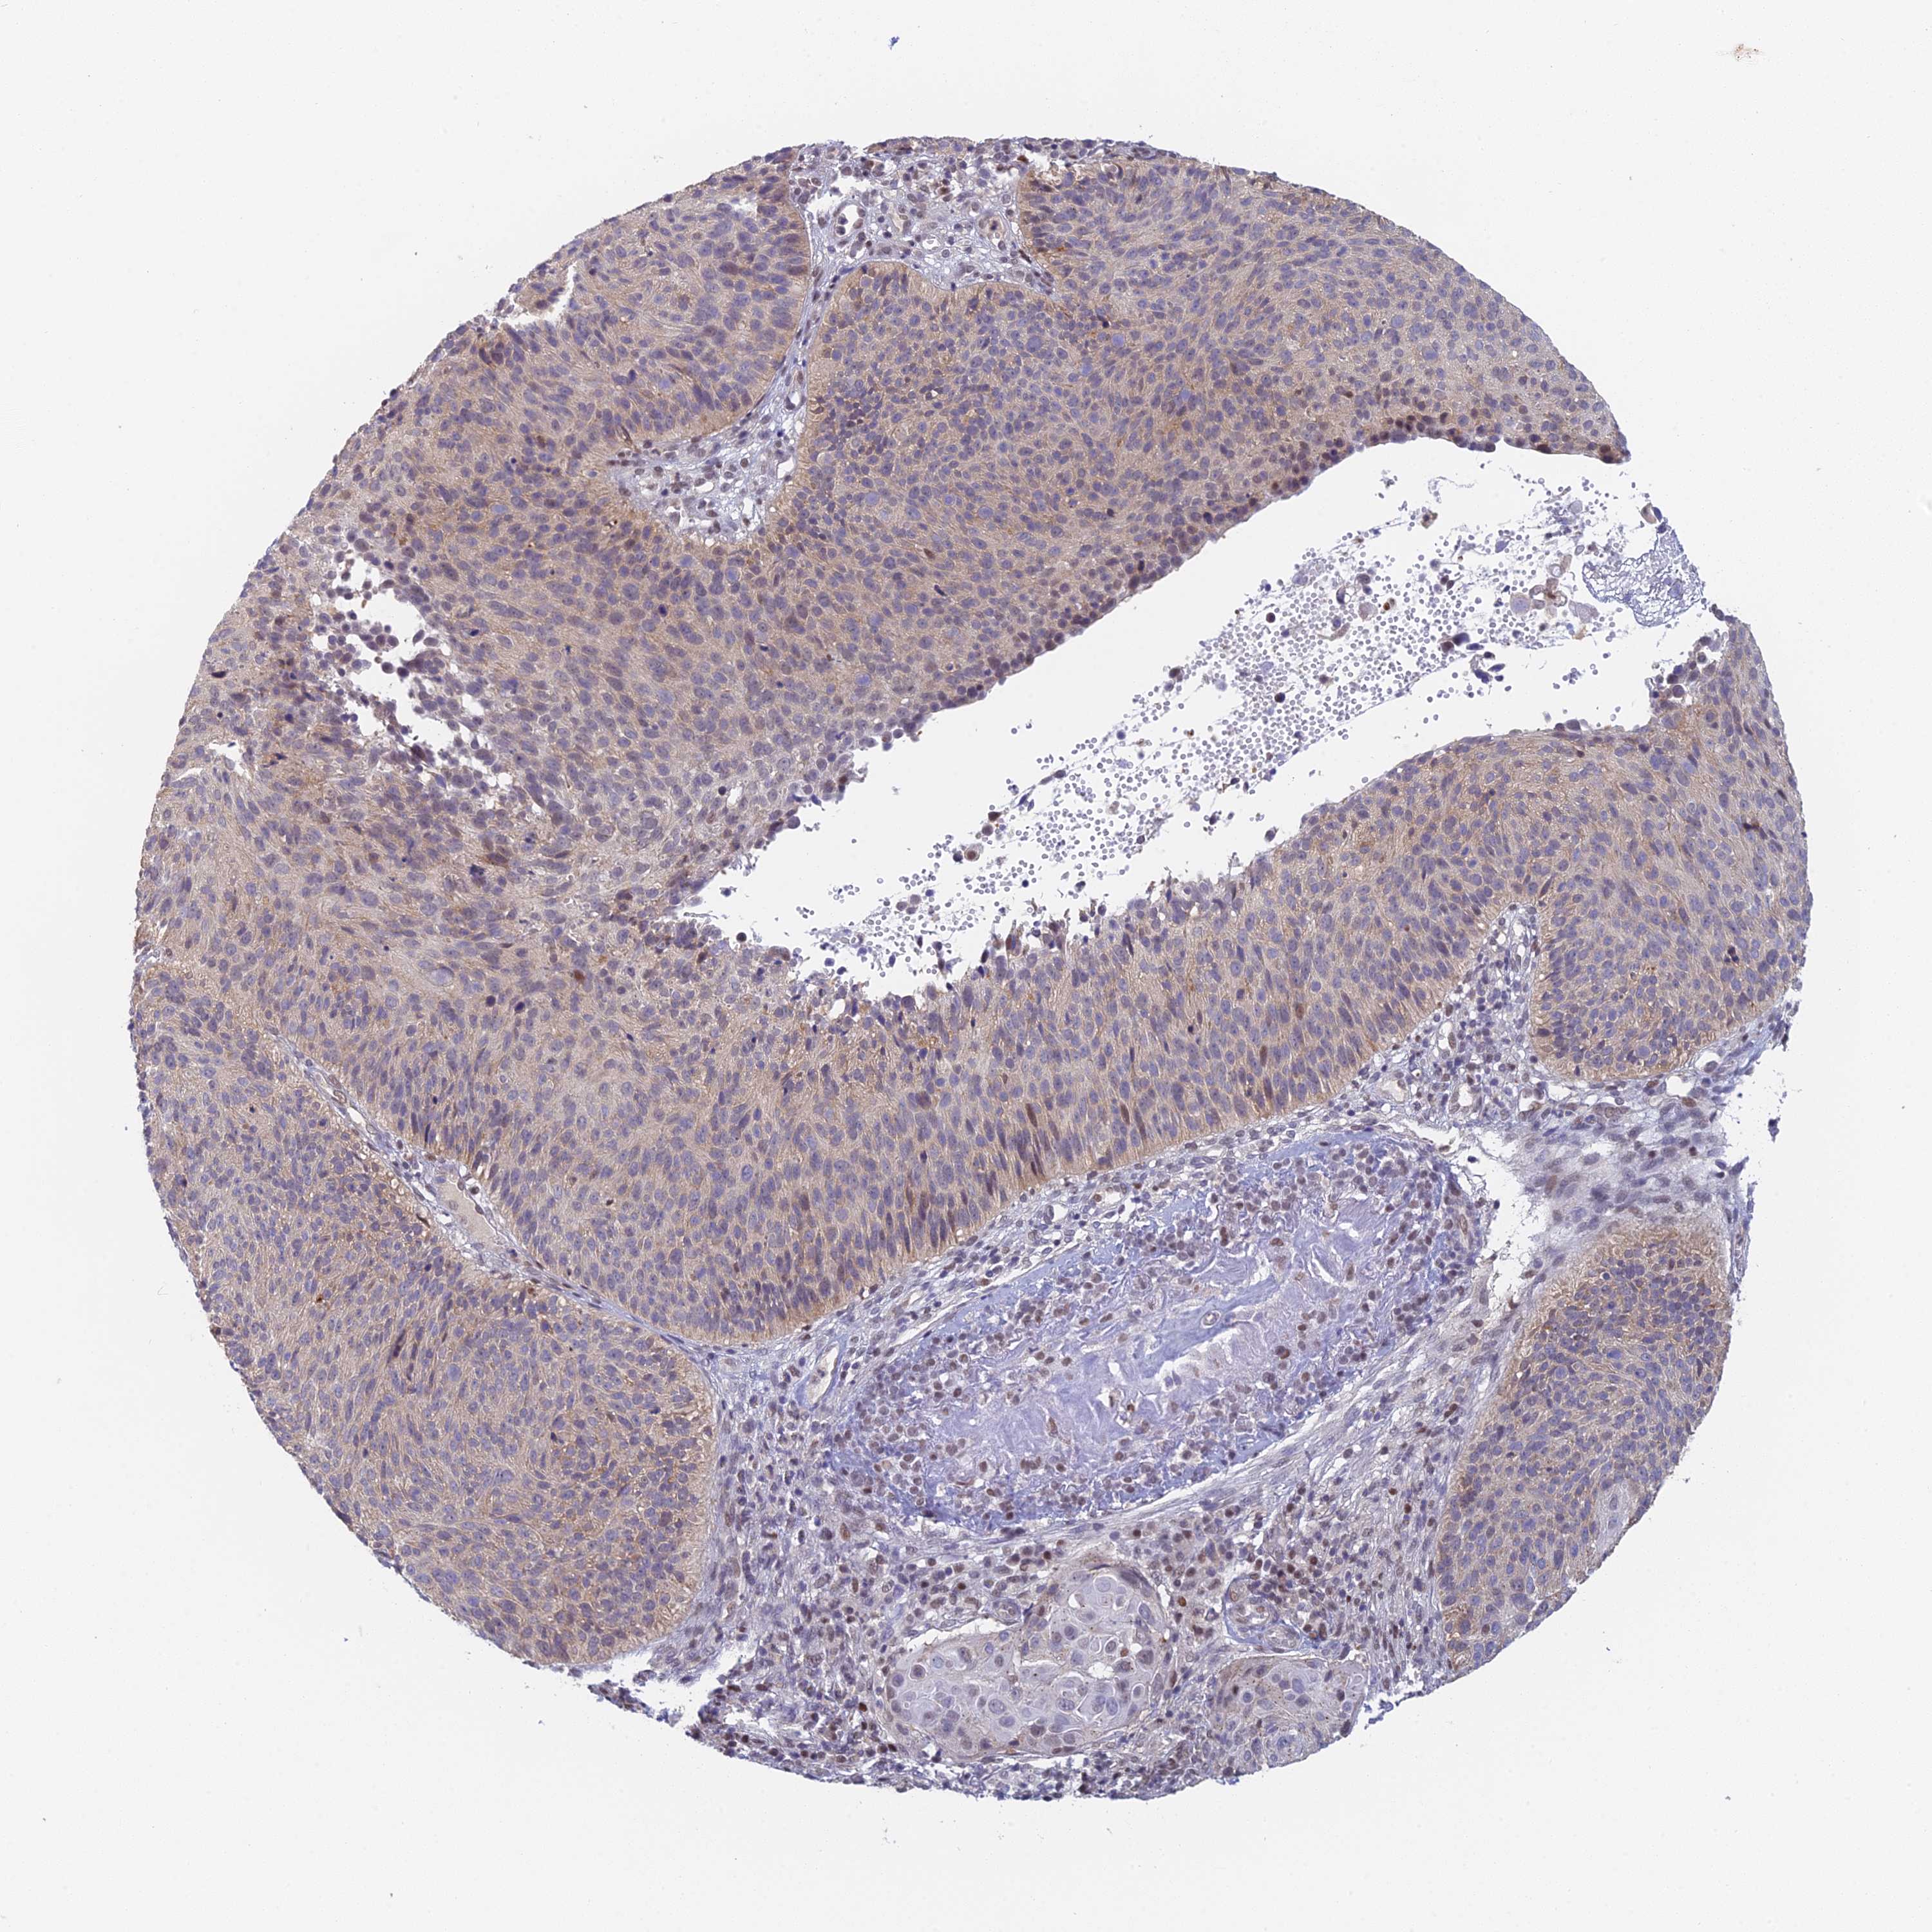

CERVICAL CANCER - Protein expressioni

A mouse-over function shows sample information and annotation data. Click on an image to view it in a full screen mode. Samples can be filtered based on level of antibody staining by selecting one or several of the following categories: high, medium, low and not detected. The assay and annotation is described here.

Note that samples used for immunohistochemistry by the Human Protein Atlas do not correspond to samples in the TCGA dataset.

Antibody stainingi

Antibody staining in the annotated cell types in the current human tissue is reported as not detected, low, medium, or high, based on conventional immunohistochemistry profiling in selected tissues. This score is based on the combination of the staining intensity and fraction of stained cells.

Each image is clickable and will lead to virtual microscopy that enables deeper exploration of all samples and also displays staining intensity scores, fraction scores and subcellular localization as well as patient and tissue information for each sample.

Antibody HPA043666

Antibody HPA050552

Squamous cell carcinoma, NOS

Adenocarcinoma, NOS